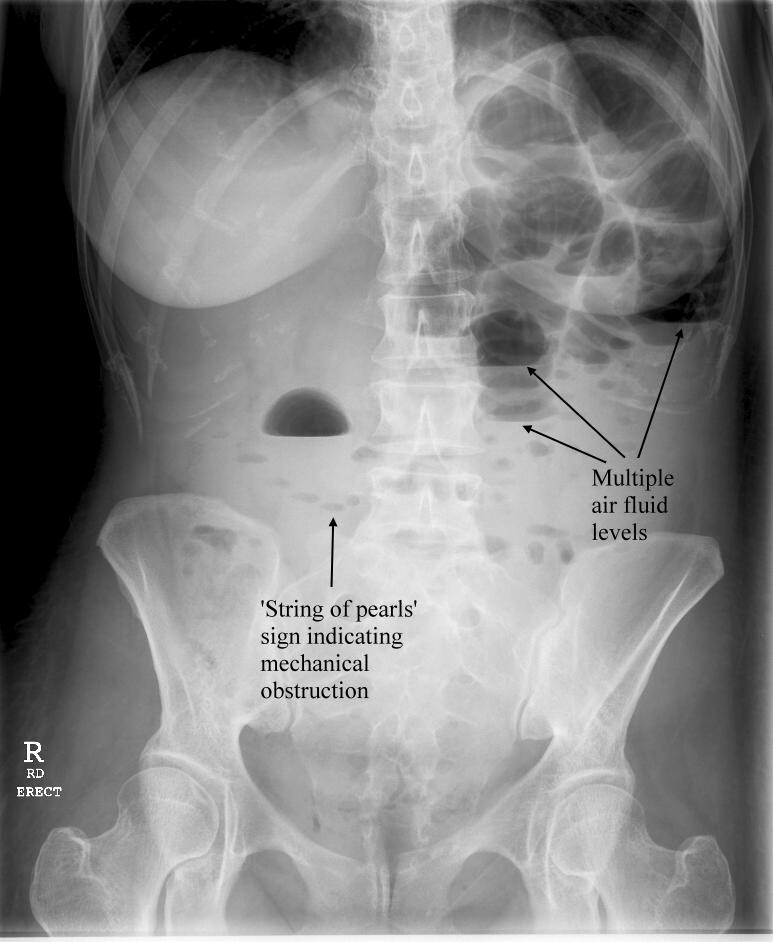

Mechanical small bowel obstruction related to abdominal masses, recommend additional follow-up or biopsy.